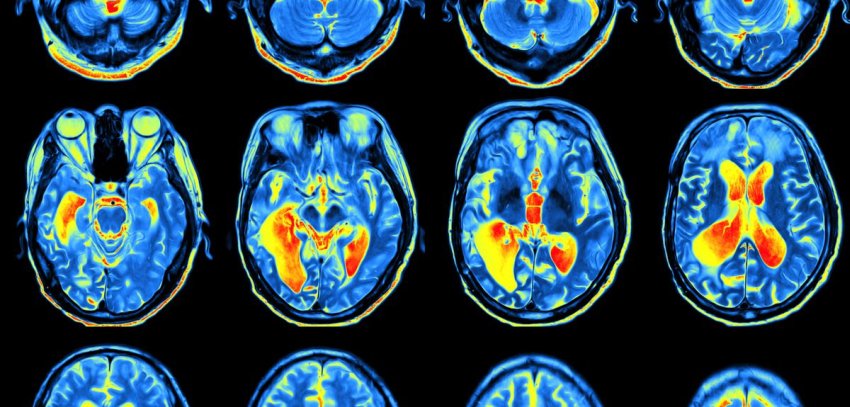

Uno studio pubblicato in Neurology insieme a un editoriale di accompagnamento riferisce informazioni importanti che possono aiutare a progettare tali test. Sono state fatte osservazioni longitudinali (=nel tempo) in partecipanti cognitivamente normali con un'età media di 72 anni (±6) per circa 7 anni, con scansioni multiple di amiloide e tau, e test cognitivi annuali e completi.

Man mano che l'Aβ diventava rilevabile nelle scansioni PET, i test cognitivi come il Digital Symbol Substitution Test (DSST) e il Trail Making Test Part A mostravano evidenze del rallentamento della velocità di elaborazione neurale mentre i test di memoria rimanevano normali. Quando le scansioni PET tau in seguito sono diventate positive, i problemi di memoria sono diventati evidenti.

Una possibile spiegazione è che l'amiloide interferisce con la trasmissione sinaptica rallentando così la velocità di elaborazione dei neuroni. La tau appare più tardi quando i neuroni iniziano a morire. Le scansioni PET sono strumenti di ricerca meravigliosi, ma sono troppo costose e ingombranti per essere pratiche per il rilevamento diffuso.